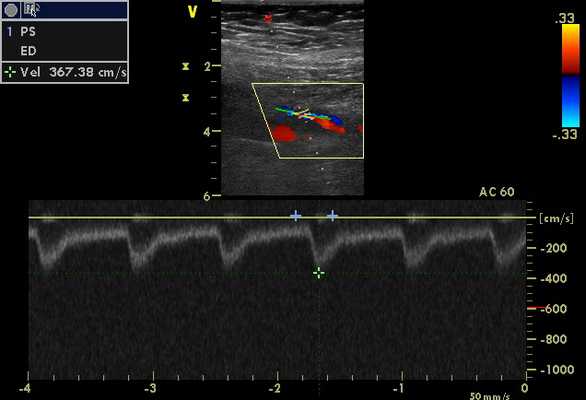

Для оценки сосудов на предмет нарушений кровотока и стенозов при васкулитах следует использовать спектральную допплеровскую визуализацию и методы визуализации цветного потока. Цветное допплеровское картирование можно быстро использовать для определения общих режимов кровотока, а также для обнаружения турбулентного потока, увеличенного кровотока, потока вне сосуда или отсутствия потока. Для определения максимальной пиковой систолической скорости (ПСС) для каждого исследуемого сосуда необходимо использовать спектральный допплер. Также может потребоваться регистрация конечной диастолической скорости (КДС), особенно если наблюдаются паттерны потока с аномально высоким или низким сопротивлением. В областях с подозрением на стеноз ПСС следует регистрировать перед интересующей областью, в области максимальной ПСС и дистальнее этой области. Также следует задокументировать постстенотическую турбулентность.